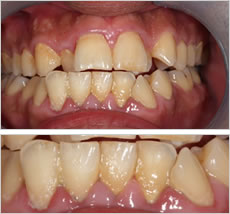

歯周病治療による効果

Before

プラークコントロール不良により、歯の周りにプラーク、歯石の付着がみられます。歯ぐきが赤く腫れあがっています。